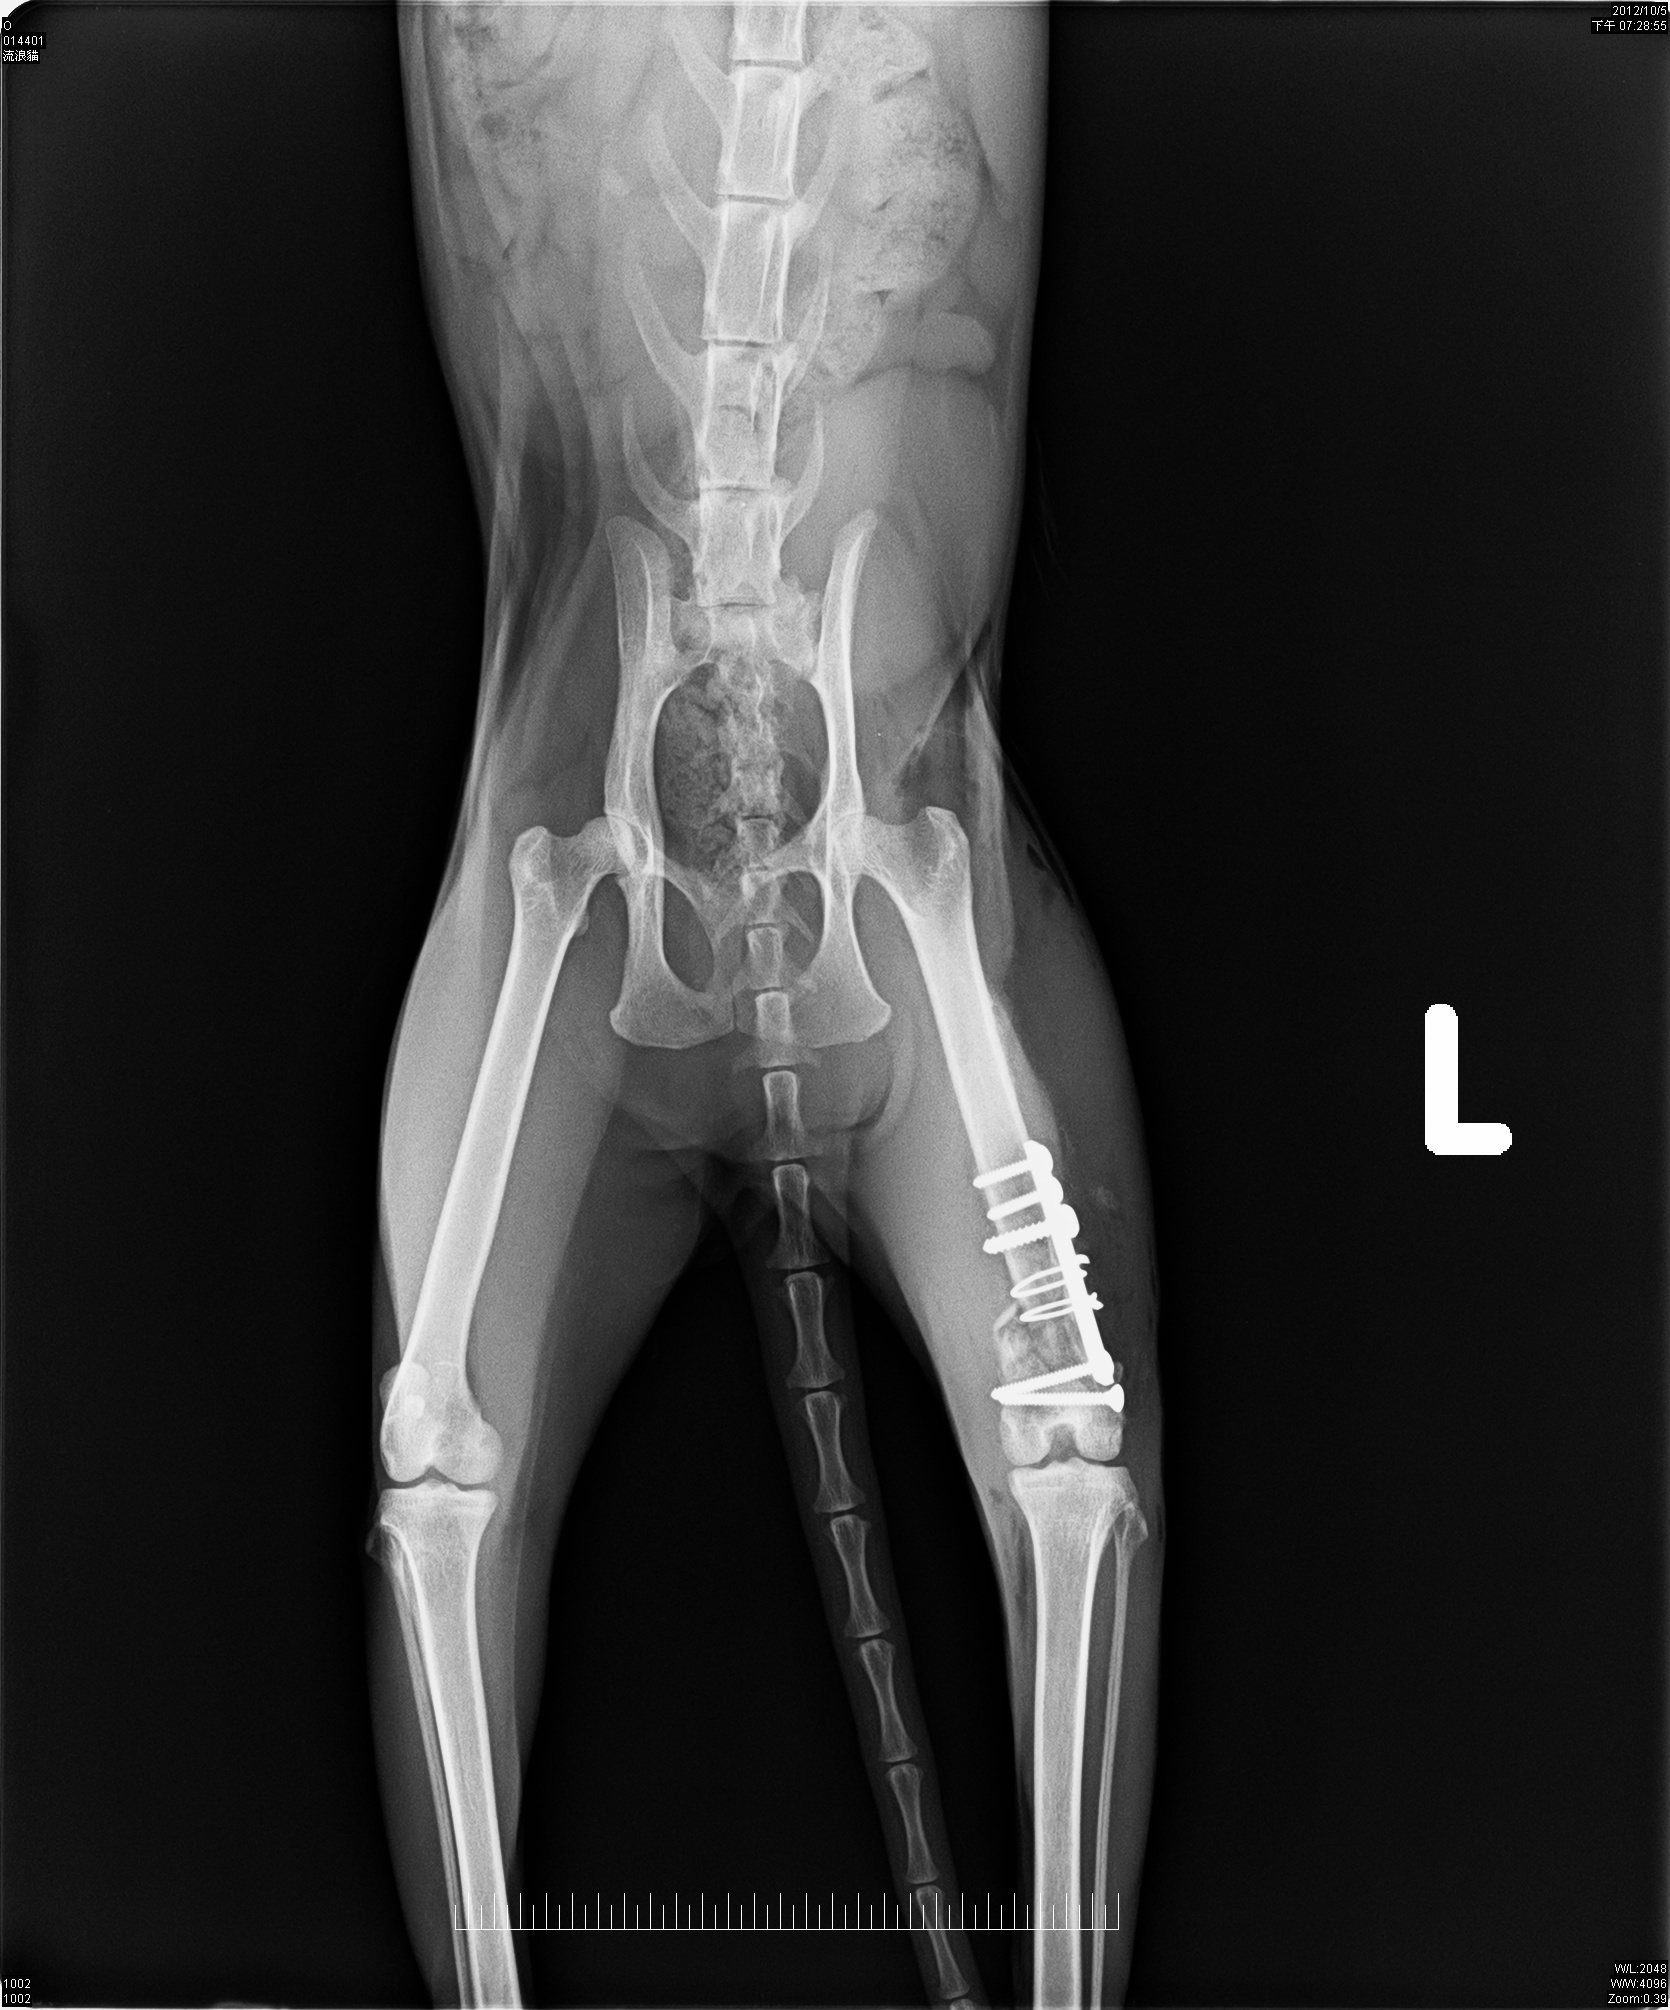

在醫院拍了X光片才得知虎斑妹妹的腳斷了,骨頭有粉碎需要開刀並打上鋼釘;但因為虎斑妹妹太瘦弱,所以先做結紮手術後,在醫院休養了幾天再安排手術!!!

10/05住院點滴止痛......................800*1天(原收費1500/天)

10/05左股骨遠端骨折手術.......10000*1次(原收費15000)

10/6~10/12住院點滴治療..............500*7天(原收費1000/天)

10/13~11/15住院治療....................300*34天(原收費500/天)

X-ray 4張.....................................優待不計(原收費400/張)

總計:800+10000+3500+10200=24500